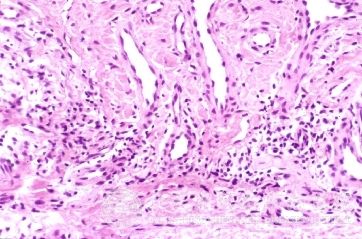

北京京城皮肤医院指出,男性同性恋生殖部位疱疹的发病特点:男性同性恋可出现肛门直肠HSV-2感染,生殖部位疱疹发病率仅次于淋球菌所致的肛门直肠炎,临床表现为肛门直肠疼痛、便秘、分泌物增加和里急后重,肛周可有疱疹性溃疡,乙状结肠镜检常见直肠下段粘膜充血、出血和溃疡。